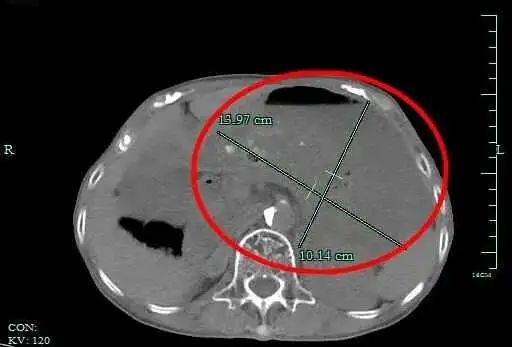

就这样吃了一个双休日,小丽感觉胃十分胀,上腹部还隐隐疼痛。难受得不行,小丽在家人陪同下,来到杭州市一集团瓶窑院区(余杭三院)就诊。消化内科孙国明医生接诊后,检查发现,小丽的胃里有大量没有消化的食物,胃腔比空腹状态扩大近40倍。

最后股点网,小丽被诊断为“急性胃扩张”,入院治疗。所幸,经治疗后,小丽腹痛症状得以缓解,没有造成其他严重后果。

余杭三院消化内科主任段阳日介绍,我们的胃像一个具有超强伸缩能力的“储物袋”。在空腹状态下,成人的胃内容量约50毫升左右,拳头大小。正常进餐后,胃容量最大可以增大近30倍,约1500毫升。

但胃容量是有限的,如果一次吃太多东西,会使得胃壁各层膨胀比例不一,最里面黏膜层和其它层分离、缺血坏死,胃也就无法自行排空食物。 就好比一只气球,如果不断为其充气,达到极限时股点网,气球壁就会变薄,并随时可能破裂。临床称之为急性胃扩张。